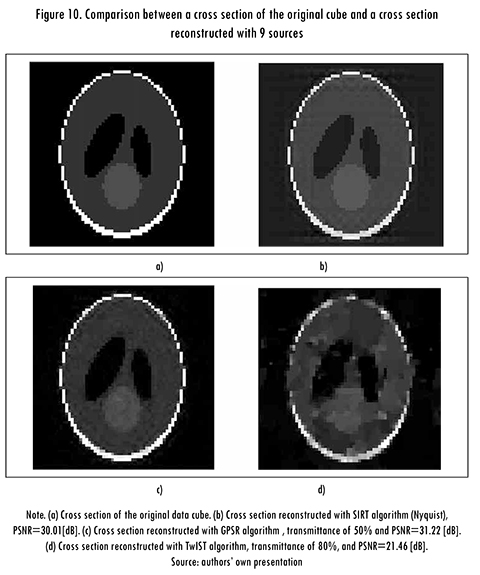

Results of reconstructed cross sections of the synthetic data cube are presented in Figure 10. Figure 10a shows a cross section of the original data cube, Figure 10b shows a cross section reconstructed with the SIRT algorithm (traditional method), using a source array of 3 X 3 (PSNR = 30.01 [dB]); Figure 10c shows a cross section reconstructed with the GPSR algorithm, using a source array of 3 X 3 and coded apertures with transmittance of 50% (PSNR = 31.22 [dB]); and Figure 10d shows a cross section reconstructed with the TwIST algorithm, using a source array of 3 X 3 and coded apertures with transmittance of 80% (PSNR = 21.46 [dB]). It can be noted the quality of the reconstructed image with the GPSR algorithm is higher than the quality obtained by other algorithms.